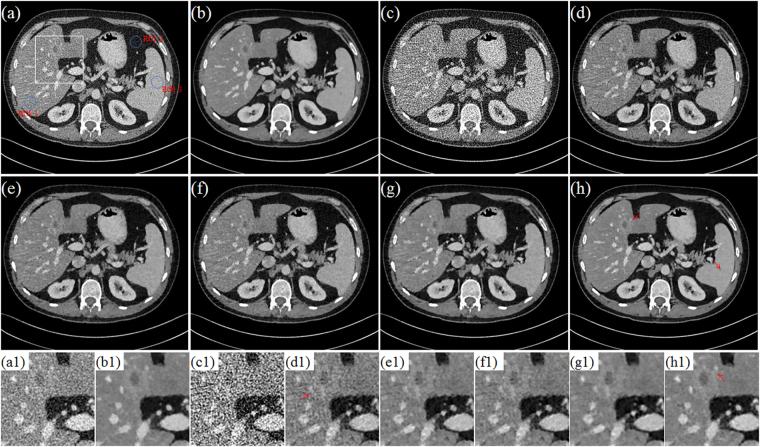

X-ray computed tomography (CT) has been widely used to provide patient-specific anatomical information in the forms of tissue attenuation. However, the cumulative radiation induced in CT scan has raised extensive concerns in recently years. How to maintain reconstruction image quality is a major challenge for low-dose CT (LDCT) imaging. Generally, LDCT imaging can be greatly improved by incorporating prior knowledge in some specific forms. A joint estimation framework termed discriminative prior-prior image constrained compressed sensing (DP-PICCS) reconstruction is proposed in this paper. This DP-PICCS algorithm utilizes discriminative prior knowledge via two feature dictionary constraints which built on atoms from the samples of tissue attenuation feature patches and noise-artifacts residual feature patches, respectively. Also, the prior image construction relies on a discriminative feature representation (DFR) processing by two feature dictionary. Its comparison to other competing methods through experiments on low-dose projections acquired from torso phantom simulation study and clinical abdomen study demonstrated that the DP-PICCS method achieved promising improvement in terms of the effectively-suppressed noise and the well-retained structures.

X 射线计算机断层扫描(CT)已广泛用于提供组织衰减形式的患者特定解剖信息。然而,近年来 CT 扫描引起的累积辐射引起了广泛关注。如何在保持重建图像质量是低剂量 CT(LDCT)成像的主要挑战。通常,可以通过以某些特定形式合并先验知识来大大改善 LDCT 成像。本文提出了一种称为鉴别先验-先验图像约束压缩感知(DP-PICCS)重建的联合估计框架。该 DP-PICCS 算法通过分别基于组织衰减特征补丁和噪声-伪影残差特征补丁的样本的原子构建的两个特征字典约束来利用鉴别先验知识。此外,通过对来自体模模拟研究和临床腹部研究的低剂量投影的实验,先验图像的构建依赖于两个特征字典的鉴别特征表示(DFR)处理。通过与其他竞争方法的比较,DP-PICCS 方法在有效抑制噪声和保留结构方面取得了有希望的改进。